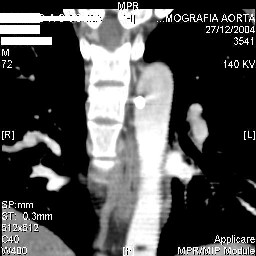

Interesting case. Findings on CT: all four pedicle screws have been placed improperly inthat they miss the vertebral bodies. In addition, the screws on the left side are impingingon the decending thoracic aorta. What I do NOT know is the nature of the original injury, orwhether or not that injury has resolved. I would recommend removal of the hardware. I don'tthink it's a good idea to leave those screws where they are. If the original fracture ishealed, nothing else needs to be done.

dear Mark, all the details are not yet available but the patient is coming to see us foradvice. We probably will see him in the early new year. i thought that the 4th picture showedthe screw to enter the aorta? He is a victim of a motor vehicle crash and thoracic vertebralfracture which appears healed. He was posteriorly decompressed and this device inserted. asyou say there isno evidenece that any of the fixation enters the bodies via the pediclesistead they have passed thru and their end are no where near where they ought to be. If I amcorrect (I would prefer not to be) the aortic intima has been breached by the screw. When thetime comes to take the screw out I thought we should have control of the aorta.What do you think?

Mark Thank you. He is scheduled for a angio prior to transfer here. I keep going back to lookat that fourth image and although it is tough to believe the wall of the aorta seems toencompass the distal 1/2 of the screw. I have come to anticipate mal postion of screws thathave been inserted in hospitals that perhaps may not have the highest quality of equipment,including the human and radiological components. That having been said this case seems tosurpass the usual... one screw out of place or screwed into a disc etc. BTW I am notsuggesting that the screw was placed directly into the aorta but that moviment, pulse actionetc may have caused it to transgress the normal anatomical bounds without evident hemorrhage.

Подошли ангиограммы... Наслаждайтесь...